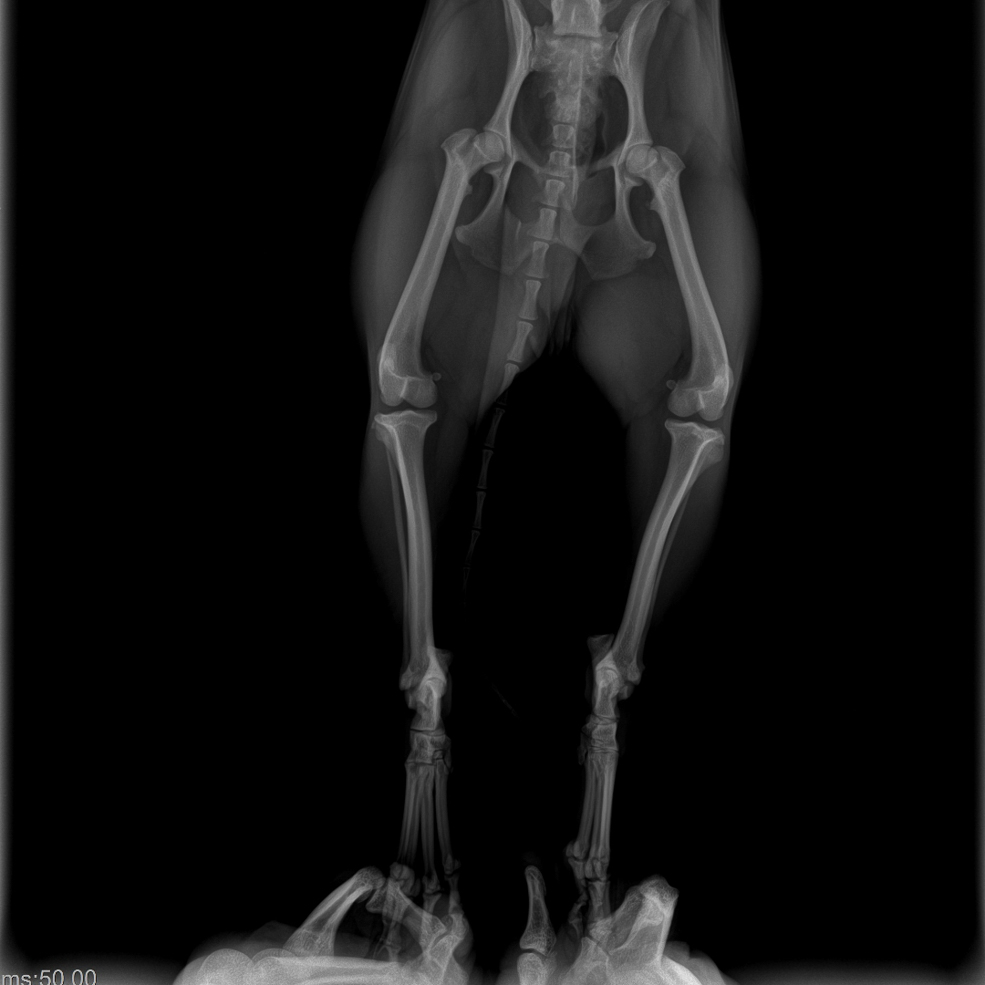

Нас встретил сотрудник Кирилл. Он полностью провёл осмотр, сделал рентген – у них есть вариант электронного снимка, когда можно приближать, рассматривать. Оказалось, что все конечности целые.